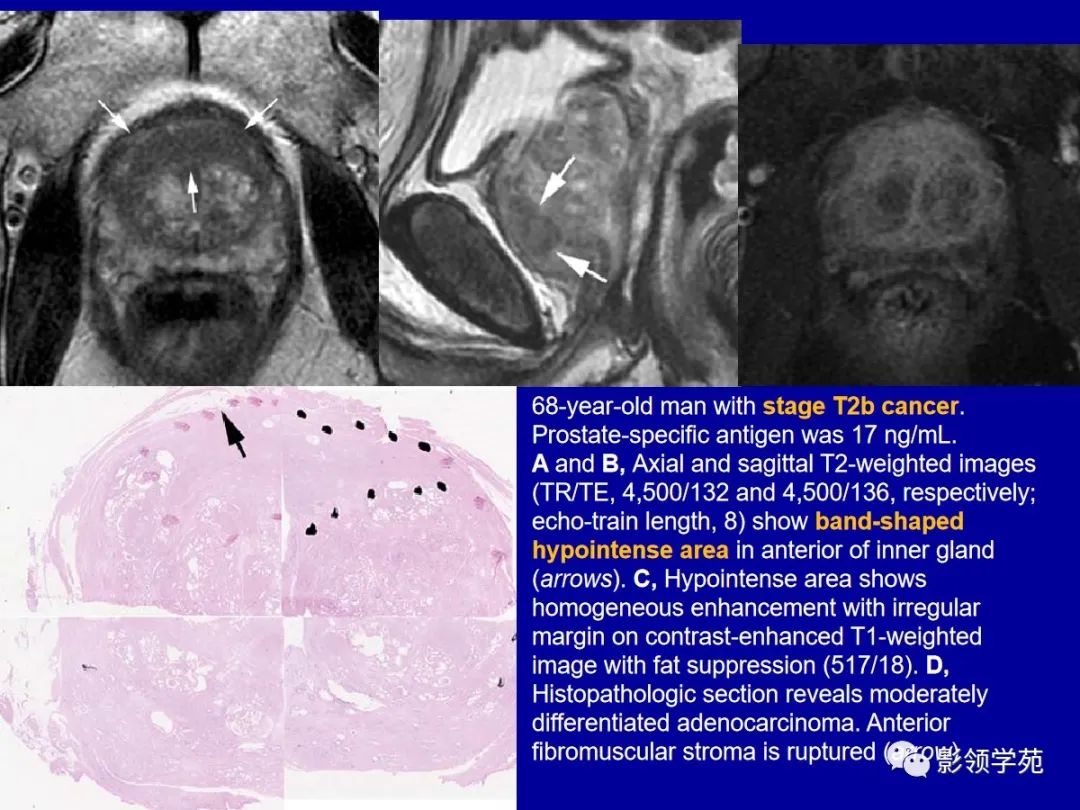

前列腺癌

图片尺寸2244x1080